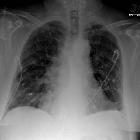

Varicella

pneumonia • Healed varicella pneumonia - miliary opacities - Ganzer Fall bei Radiopaedia

Hyperdense pulmonary nodules are a subset of pulmonary nodules that have relatively increased attenuation, usually caused by calcification within the nodule. Here, we broadly refer to a nodule as a pulmonary opacity <30 mm.